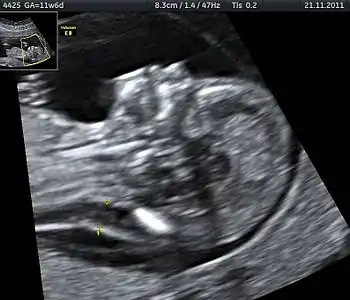

Enlarged NT and absent nasal bone in a fetus at 11 weeks with Down syndrome

Overall, the most common chromosomal disorder is Down syndrome (trisomy 21). The likelihood rises with maternal age from 1 in 1400 pregnancies below age 25, to 1 in 350 at age 35, to 1 in 200 at age 40.[4]